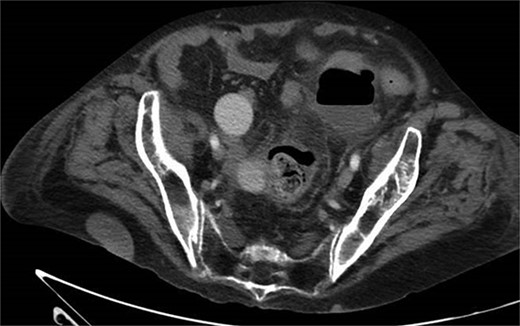

A 65-year-old female with a history of hyperlipidemia, hypertension, hip replacement, lumbar spinal fusion, chronic pain management, and prior laparotomy for endometriosis presented with a 3-day history of nausea, vomiting, and abdominal pain. She had no prior history of diverticulosis or colonoscopy. On examination, she was afebrile and hemodynamically stable. Physical examination revealed left lower quadrant tenderness, swelling, erythema, and fluctuance, suggesting an abdominal wall abscess (Figs 1 and 2). Laboratory tests showed leukocytosis with a count of 24.6 and a positive urinalysis with 2+ leukocytes. A CT scan of the abdomen and pelvis revealed a 3.8 × 3.6 cm air and fluid pocket in the low left anterior abdominal wall, indicative of an abscess likely at the site of a previous drain (Fig. 3). Additionally, there was a 2.8 × 1.8 cm irregular air pocket in the left pelvis, where an abscess had been identified in prior imaging.

CT from readmission with anterior abdominal wall abscess and left pelvic abscess.

One month prior, the patient was admitted for complicated perforated sigmoid diverticulitis. Treatment included piperacillin-tazobactam (Zosyn), bowel rest, and fluid resuscitation. On hospital Day 6, her condition worsened with increased nausea, vomiting, and an elevated WBC count of 15. CT imaging revealed a 4.8 × 4.4 × 4.0 cm diverticular abscess, leading to CT-guided percutaneous drainage by interventional radiology (Figs 4–7). Cultures grew Citrobacter sedlakii and Enterococcus faecium vancomycin resistant Enteroccus (VRE), and treatment was adjusted to include Bactrim, followed by daptomycin and levofloxacin. The abscess resolved after 3 weeks, and the drain was removed before discharge. The patient was instructed to follow up with her surgeon and undergo a 6-week interval colonoscopy.